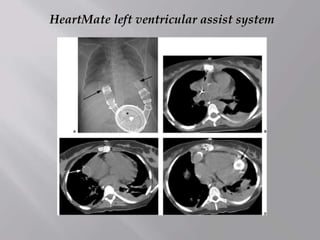

HeartMate left ventricular assist system